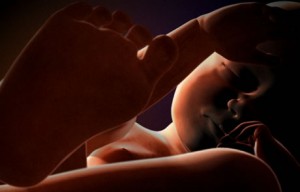

25 haftalık bebek Bebeğinizin boyu 30 cm oldu. İç kulağındaki kemiklerde sertleşmeye başladığından artık sizi daha iyi duyabiliyor. Aslında babasının sesini, sizin sesinizden daha net duyabiliyor. Eşinize söyleyin, karnınıza yaklaşıp bebeğinize “Merhaba” desin lütfen !